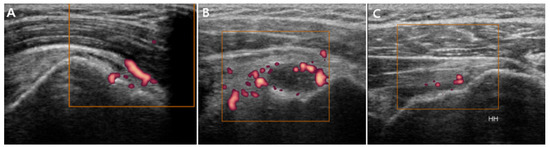

3.2.3. Power Doppler Findings